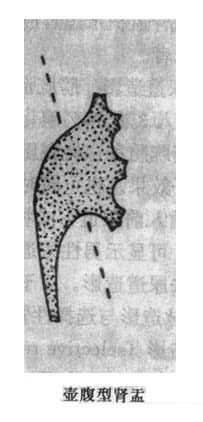

肾小盏分为体部及穹窿部。顶端由于乳头的突入而呈杯口状凹陷,边缘整齐,杯口的两缘为尖锐的小盏穹窿。肾小盏位于不同平面且指向不同方向(主要指向外方),如果肾小盏恰好面向X线束,成横断面投影(或称正位投影),则形成一个环状影或圆形致密影,勿误诊为结石。有时一个肾小盏可接受多个乳头伸入而表现为较大且不规则,多见于上、下盏。肾小盏体部较窄,又称为漏斗部。肾大盏边缘光滑整齐,略成长管状,可分三部:①顶端或尖部,与数个肾小盏相连;②峡部或颈部,即为和长管状部;③基底部,与肾盂相连。肾大小盏的形状和数目变异较多,有的粗短,有的细长,两侧肾盏的形状、数目亦常不同。但一般肾大盏常为3个。肾盂多位于第二腰椎水平,略呈三角形,上缘隆凸,下缘微凹,均光滑整齐。肾盂开头亦有较大变异,多呈喇叭状,少数可呈分支状,即肾盂几乎被两个长形肾大盏所代替。有的肾盂呈壶腹形,直接与肾小盏相连而没有肾大盏。这种肾盂勿误诊为肾盂扩大。肾盏和肾盂均有蠕动,有时其边缘可见到暂时性凹陷或狭窄,为蠕动波所成。肾血管有时亦在肾盏或肾盂边缘造成小的压迹,均属正常(图4-4-1)。

图4-4-1 正常肾盂肾盏不同形状(虚线状代表肾的内缘和肾门区)